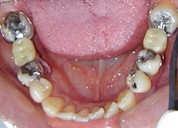

Electrogalvanismo en boca prodUcido por el

asentamiento de la prótesis de cromo cobaltosobre amalgamas

Galvanismo

por presencia de amalgamas en elmaxilar superior e inferior |